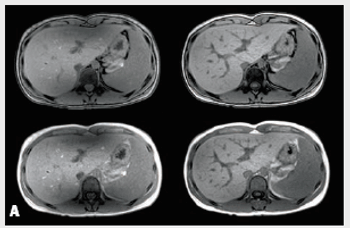

Image quality derived from echo liver imaging at 3T (A, left) improves (A, right) when applying Philips MultiTransmit technology, which eliminatesdielectric shading, an artifact commonly found at this field strength.